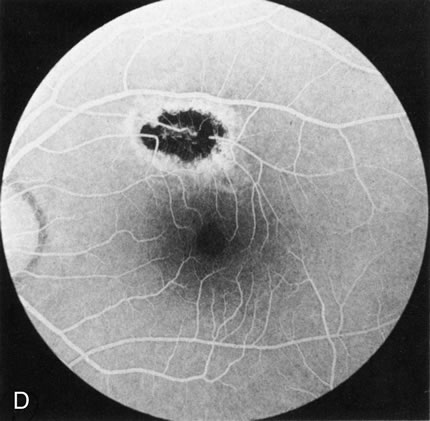

DOMINANT DRUSEN OF BRUCH'S MEMBRANE

There is no clear agreement as to what constitutes dominantly inherited drusen and what constitutes age-related degenerative drusen. There is a distinct group of younger individuals with bilateral, symmetric, uniformly small, round, discrete, yellow and white drusen. Histopathology demonstrates a nodular thickening of the RPE basement membrane, and these drusen have therefore been referred to as basal laminar, or cuticular, drusen.24

FA shows a characteristic pinpoint area of transmission hyperfluorescence corresponding to the drusen and reveals many more than are appreciated clinically (Fig. 12). Secondary changes such as pigment atrophy and dispersion, exudative and nonexudative detachments, and occasionally a neovascular membrane, will be revealed by FA (Fig. 12E).

Fig. 12. Dominant drusen of Bruch's membrane. The drusen appear as yellowish-white “blisters” predominantly in the temporal posterior pole (A). The angiogram shows many pinpoint areas of transmission hyperfluorescence typical of drusen, some of which have coalesced to form broader areas of hyperfluorescence (B). These drusen occasionally result in ingrowth of a choroidal neovascular membrane, such as occurred in this case over a 5-year period (C–E).